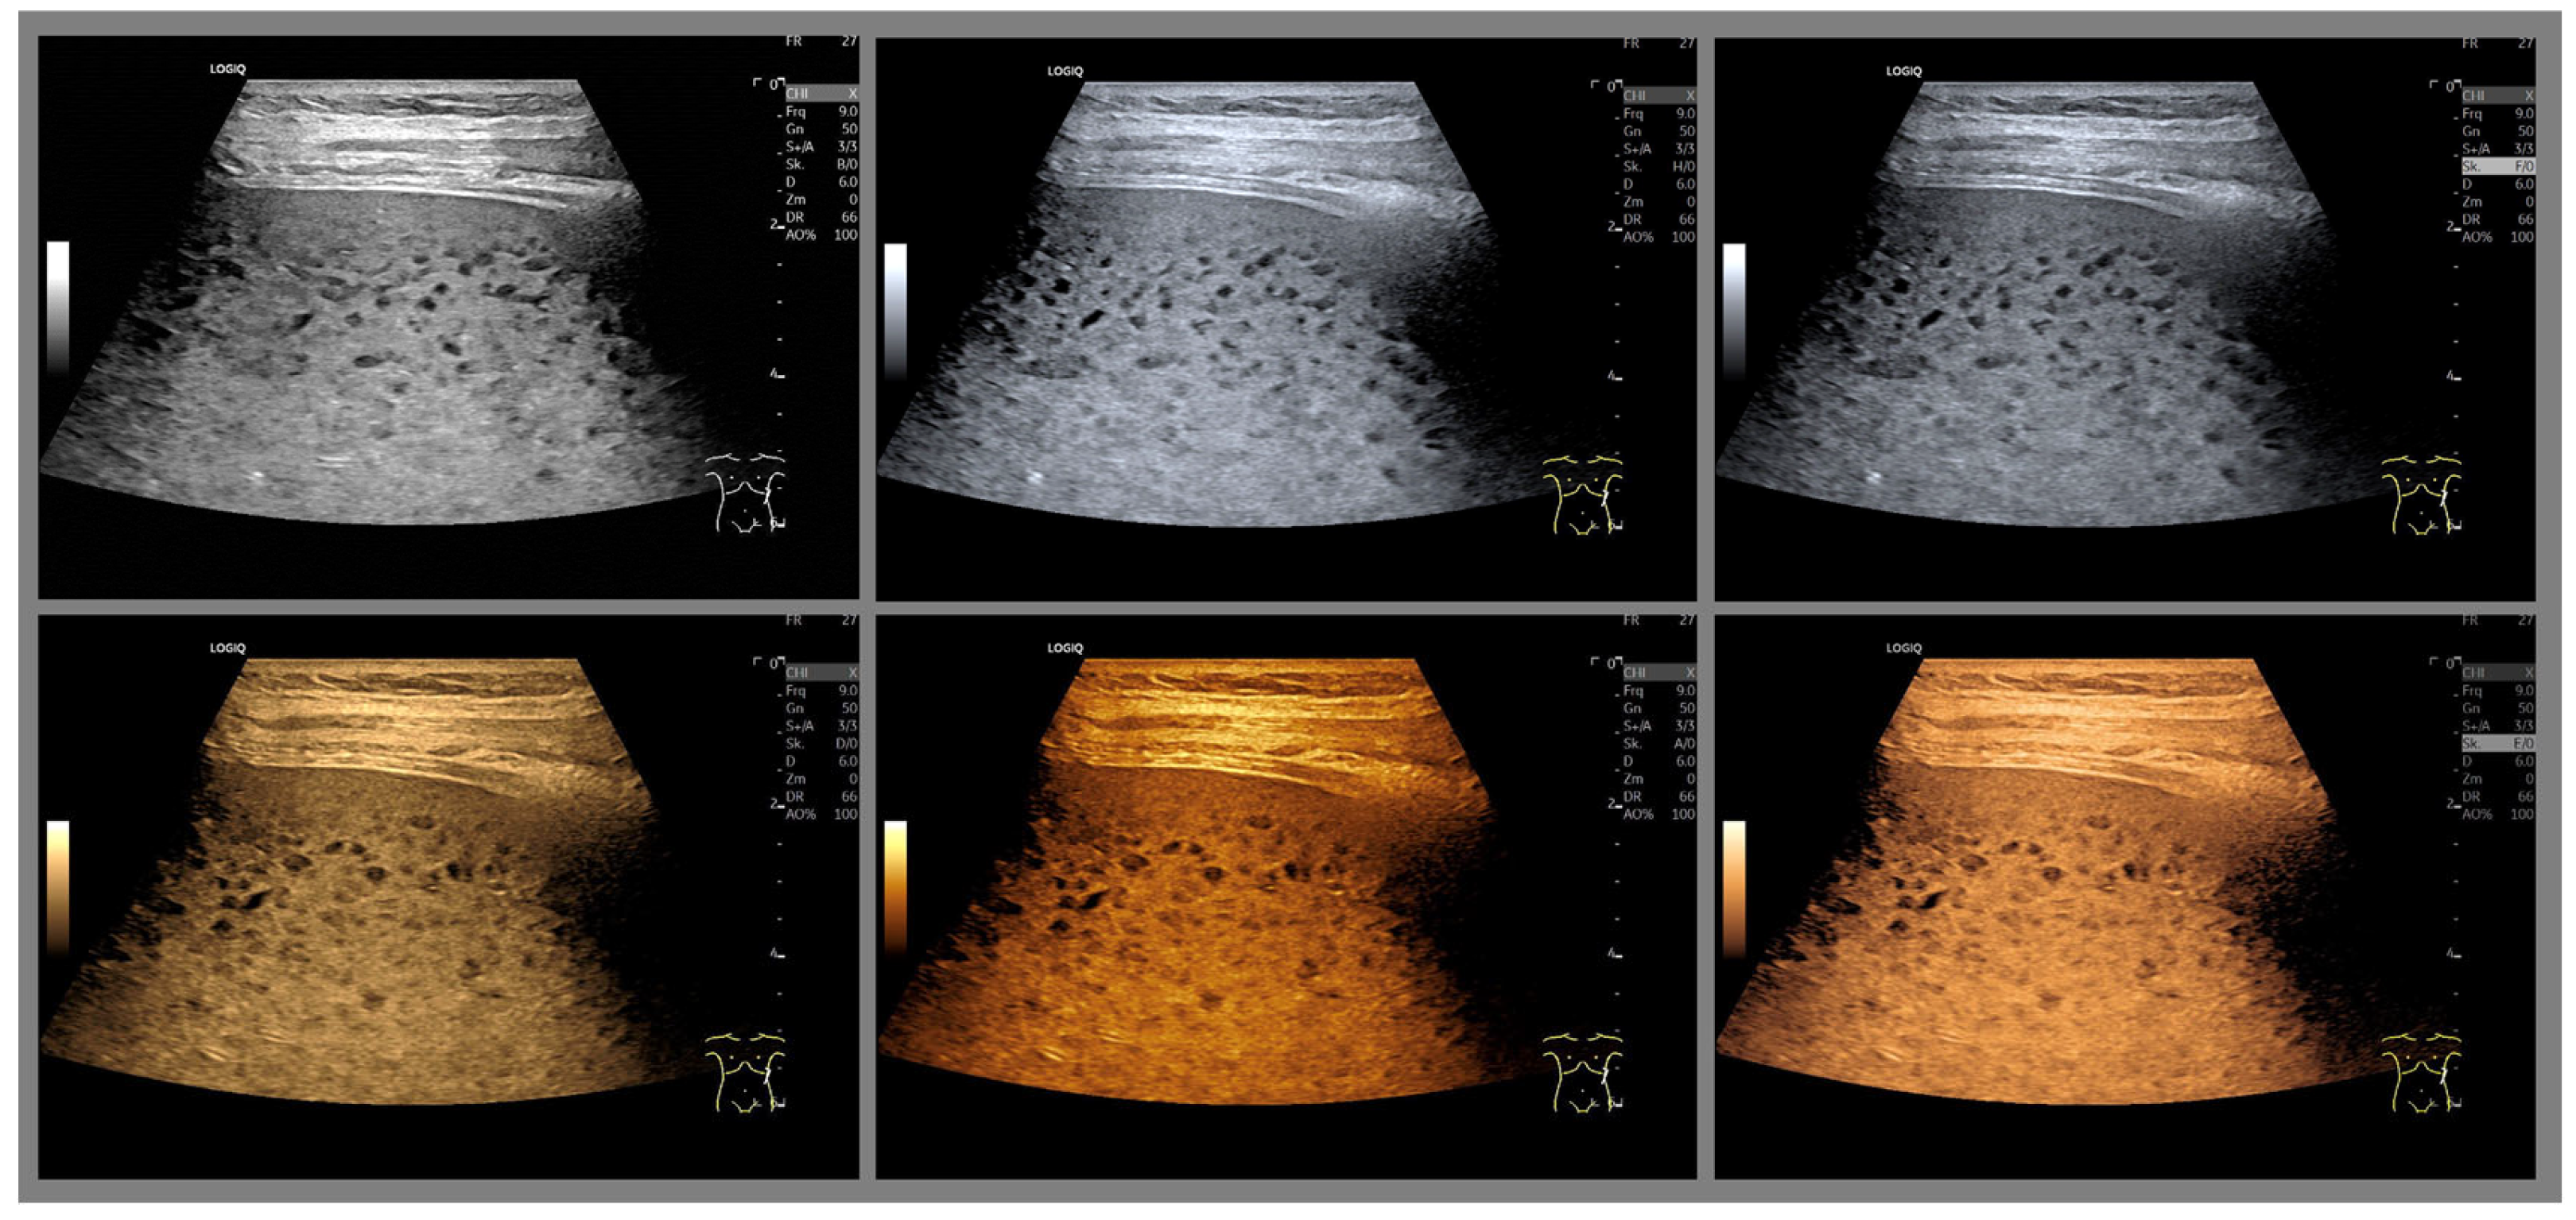

- The combination with speckle filters available in all high-end devices, similar to the low-pass filters used by Bleck et al. (1994) for tissue visualization [5], also yields significantly improved visualization results (Figure 5, Figure 6 and Figure 7). In principle, applications with new visualized texture analyses, such as random field models, are also conceivable [76,77].